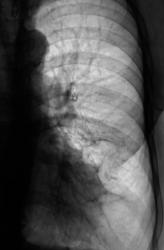

На левой боковой рентгенограмме следующая картина.

Четко дифференцируется тень осумкованного передне-базально-интерлобарного плеврита.